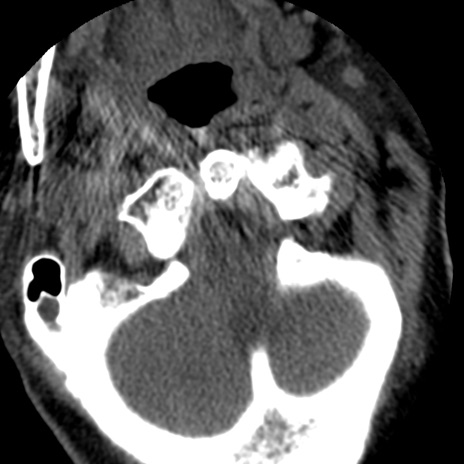

症例50 頚椎CT(横断像)

冠状断像